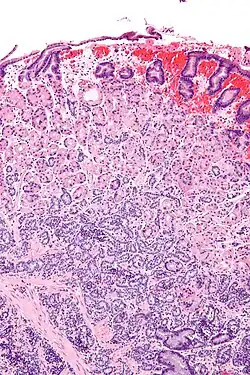

![]() Micrografía de un tumor neuroendocrino gástrico. Tinción H&E. | ||